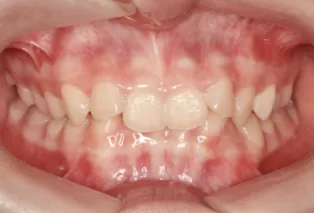

Photos intra-orales